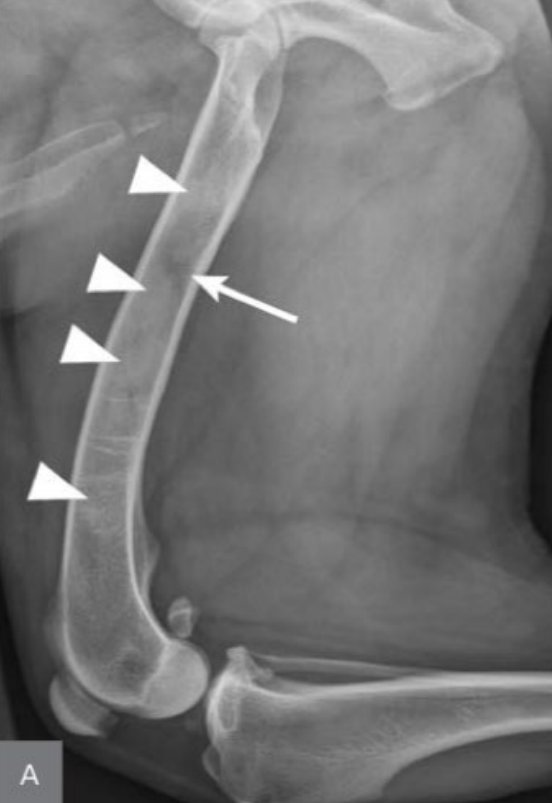

사진 모음

- arrow : 두꺼워진 골막

- arrowhead : 뿌옇게 보이는 골수관

- 범골염, 앞다리 전체 범위

- 골수관의 불규칙 패턴

- 노뼈와 자뼈가 겹쳐보여 구별 어려움 (시험용X)